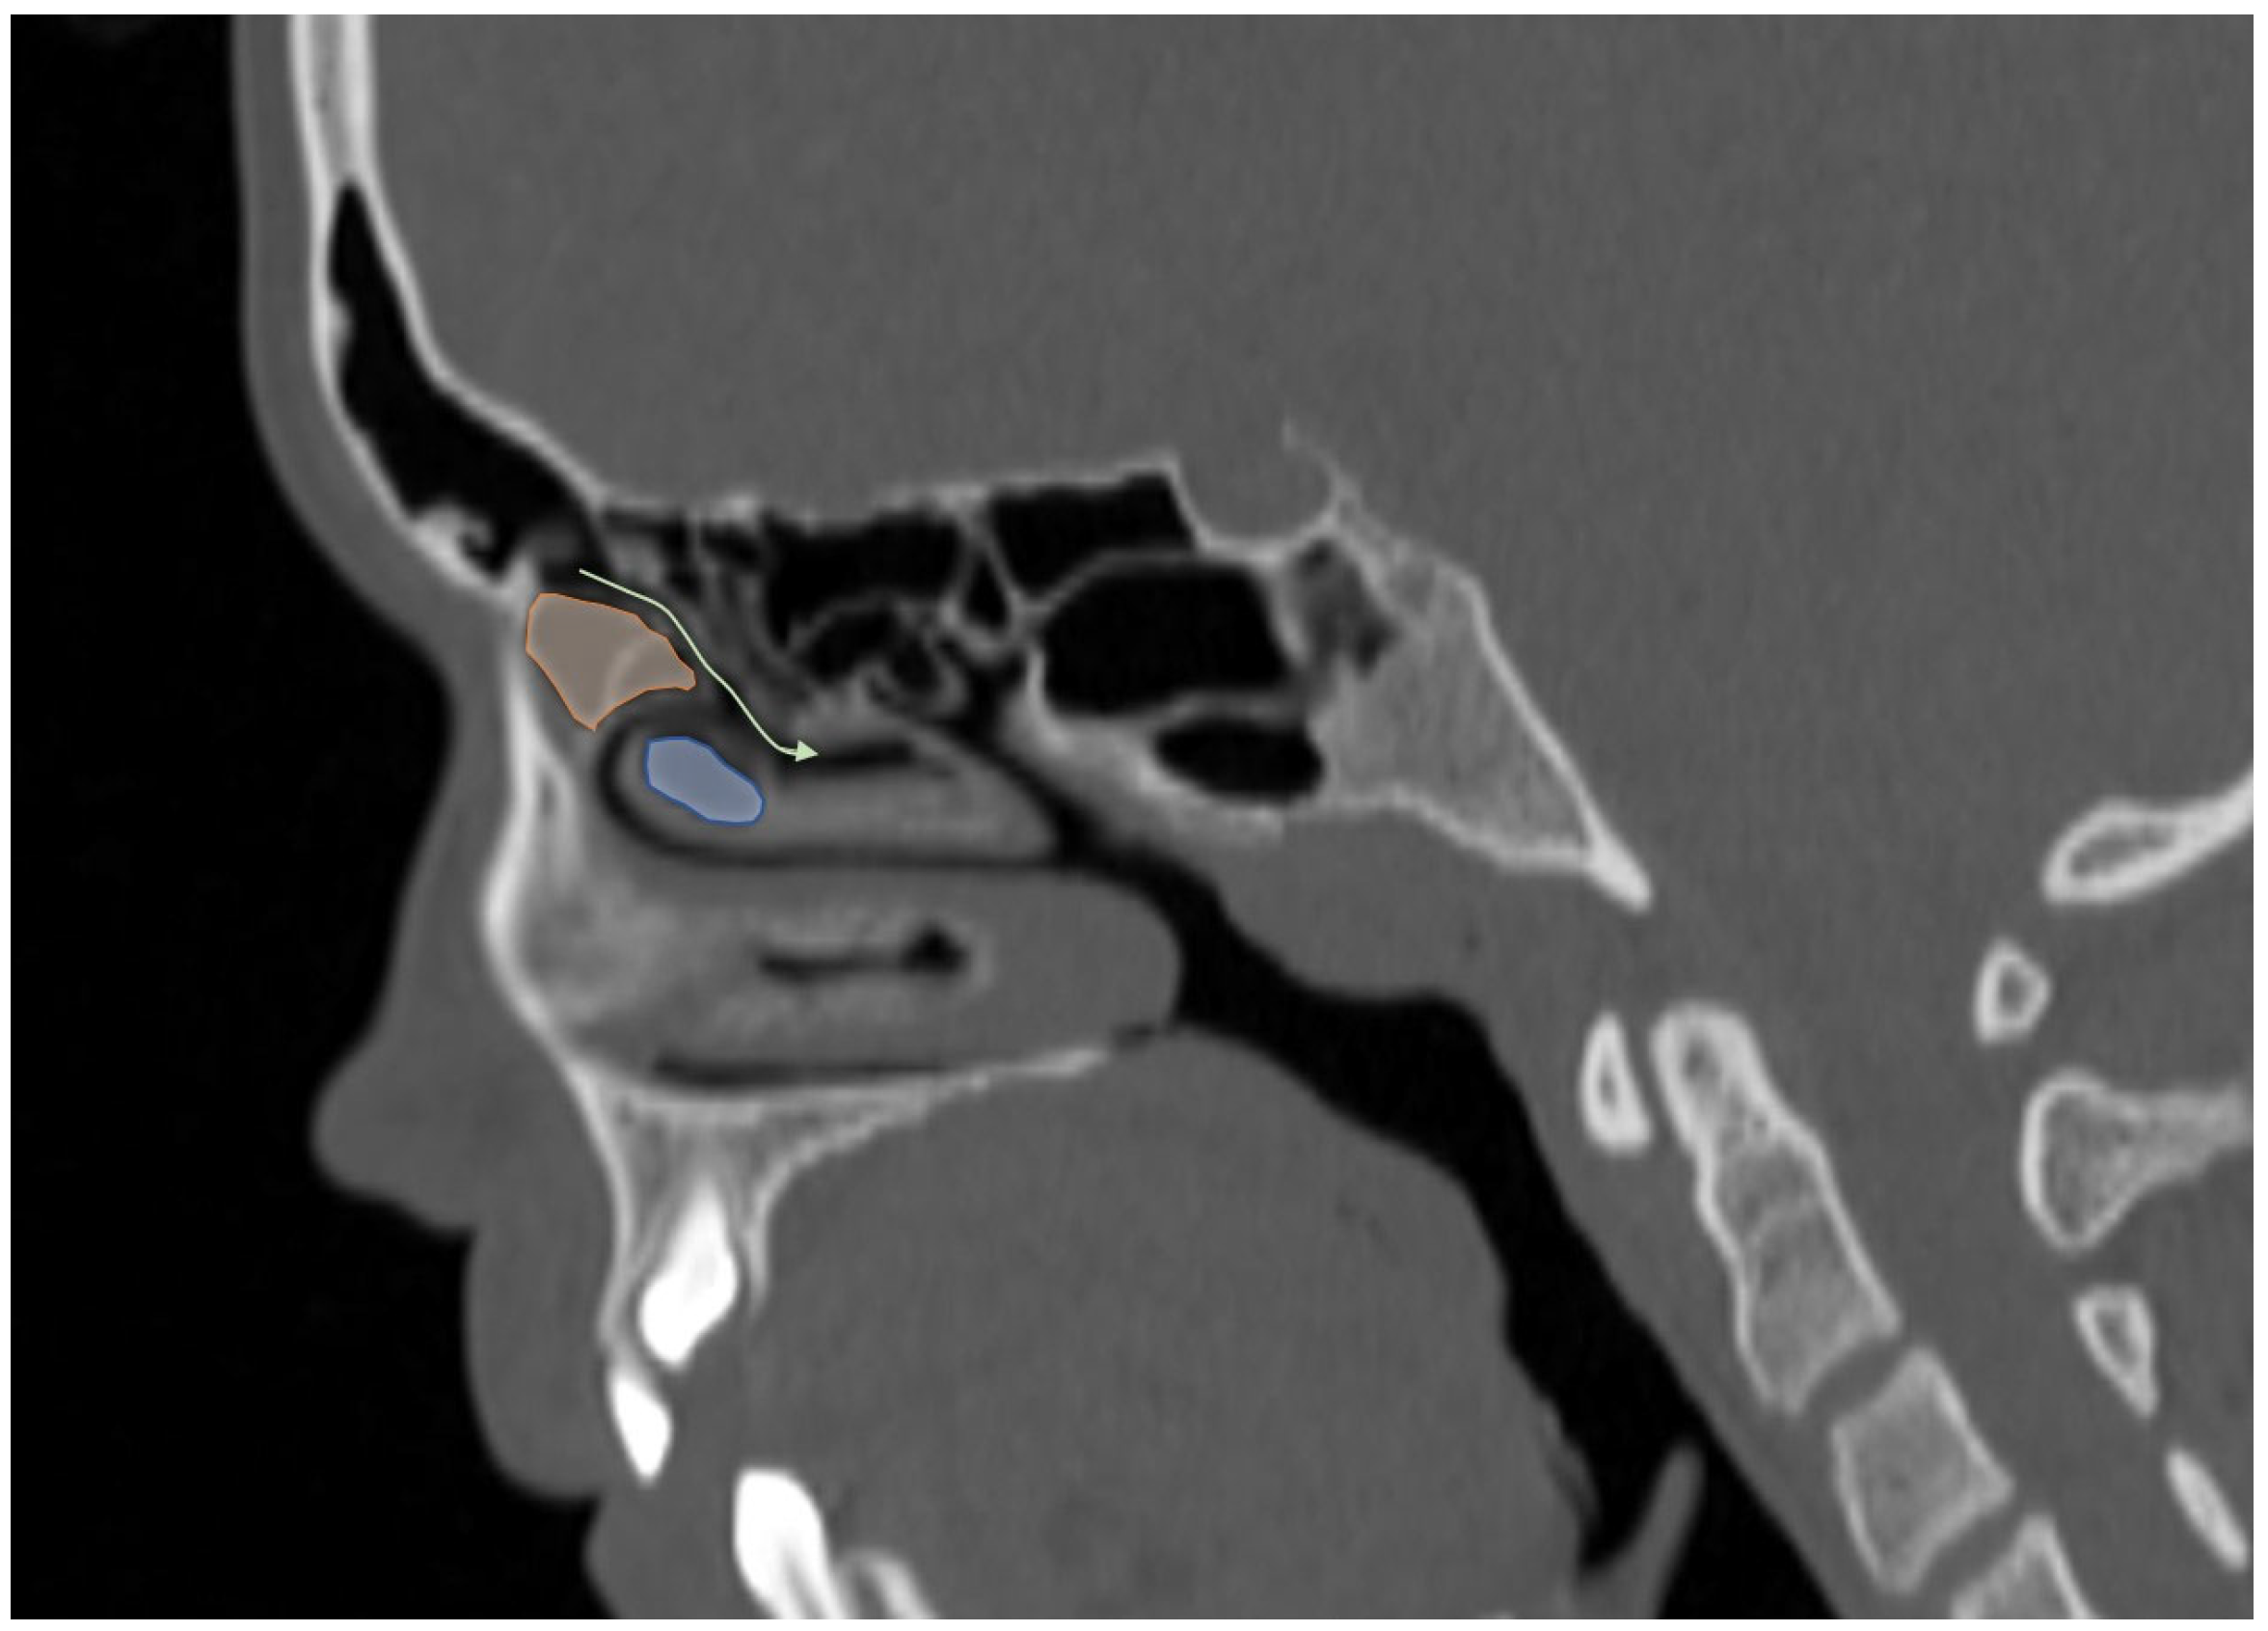

Additionally, the images were assessed for the presence of anatomic variants of the nasal cavity and PNS. Sinonasal variations were defined based on the European Position Paper on the Anatomical Terminology of the Internal Nose and Paranasal Sinuses [19]. According to this paper, the maxillary sinus is located between the orbital floor and alveolar process of the maxilla; the sphenoid sinus is the pneumatization of the sphenoid bone posterior to the rostrum; and the frontal sinus is defined as the pneumatization superior to a noticeable frontal beak [11,19]. The ANs are defined as the aeration of the protuberance on the lateral nasal wall, slightly anterior to the middle turbinate attachment (Figure 4). The Haller cell is an ethmoidal air cell, located below the orbital floor and lateral to a line parallel with the lamina papyracea (Figure 5). Onodi cell is the posteriorly located ethmoidal cell which develops just above and lateral to the sphenoid sinus (Figure 6). Concha bullosa is the pneumatization of the vertical segment of the middle turbinate (Figure 7) [19]. All anatomical variants were initially assessed by a single radiologist with four years of experience in maxillofacial CT imaging, who was blinded to patients’ demographic data, including age and sex. All assessments were done on a DICOM viewer (Medixant. RadiAnt DICOM Viewer [Software]. Version 2024.1. URL: https://www.radiantviewer.com (accessed on 1 November 2024)), after retrieval from the hospital PACS system to provide anonymized evaluation. The prevalence of each variant and the frequency of its bilaterality in each group were recorded. The evaluations were subsequently reviewed by a second radiologist with 11 years of experience. In cases of uncertainty regarding the presence of anatomical variations, a consensus decision was reached in consultation with a third radiologist with 13 years of experience.

Figure 4.

Sagittal reformatted CT image of a 14-year-old girl showing Agger Nasi cell (orange area) in front of the frontal recess draining into the middle meatus (curved arrow) and concha bullosa (blue area).